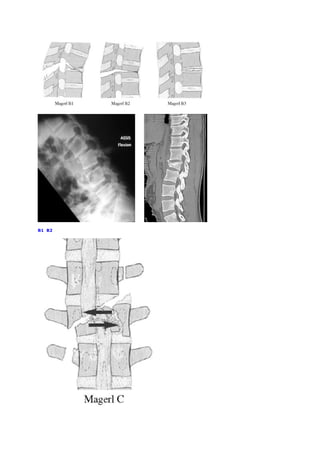

Nous utilisons préférentiellement la classification de Magerl qui est basée sur le

mécanisme lésionnel, comportant 3 groupes principaux subdivisés. Le groupe A

correspond à un mécanisme en compression (les lésions siégeant surtout au

niveau du corps vertébral) allant de la simple fracture du plateau supérieur (A1)

à la burst fracture (fracture comminutive) (A3). Le groupe B correspond aux

fractures par distraction. Il est divisé en trois groupes distincts, les lésions en

flexion-distraction postérieure à prédominance ligamentaire B1, les lésions en

flexion-distraction postérieure à prédominance osseuse B2 et des lésions en

hyperextension avec distraction antérieure B3. Enfin, le groupe C correspond

aux lésions résultant d’un mécanisme en rotation ajouté aux mécanismes des

types A et B. Cette classification a un caractère pronostic, les subdivisions sont

de                     gravité                     croissante.